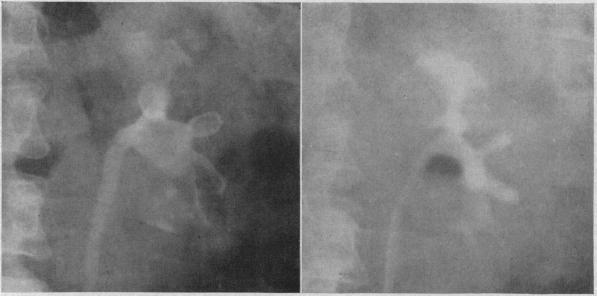

Immediate steps in the treatment of ureteral stone, beginning with the often acute onset, are relief of pain, urinalysis (including Gram stain), forcing fluids, examination of urine for the stone and urography at the earliest feasible time. If the stone causes continual pain or appears unlikely to be passed safely, it should be removed-with a cystoscope if possible; if not, by operation which may be done while the patient is still under anesthesia. To combat further stone formation a large fluid intake should be maintained, the extracted stone analyzed, an acid ash diet prescribed, serum calcium and phosphorus measured, urinary stasis corrected and urinary infection and distant foci of infection cured. Vitamin A, aluminum gels and particularly hyaluronidase appear promising as preventives to stone formation.